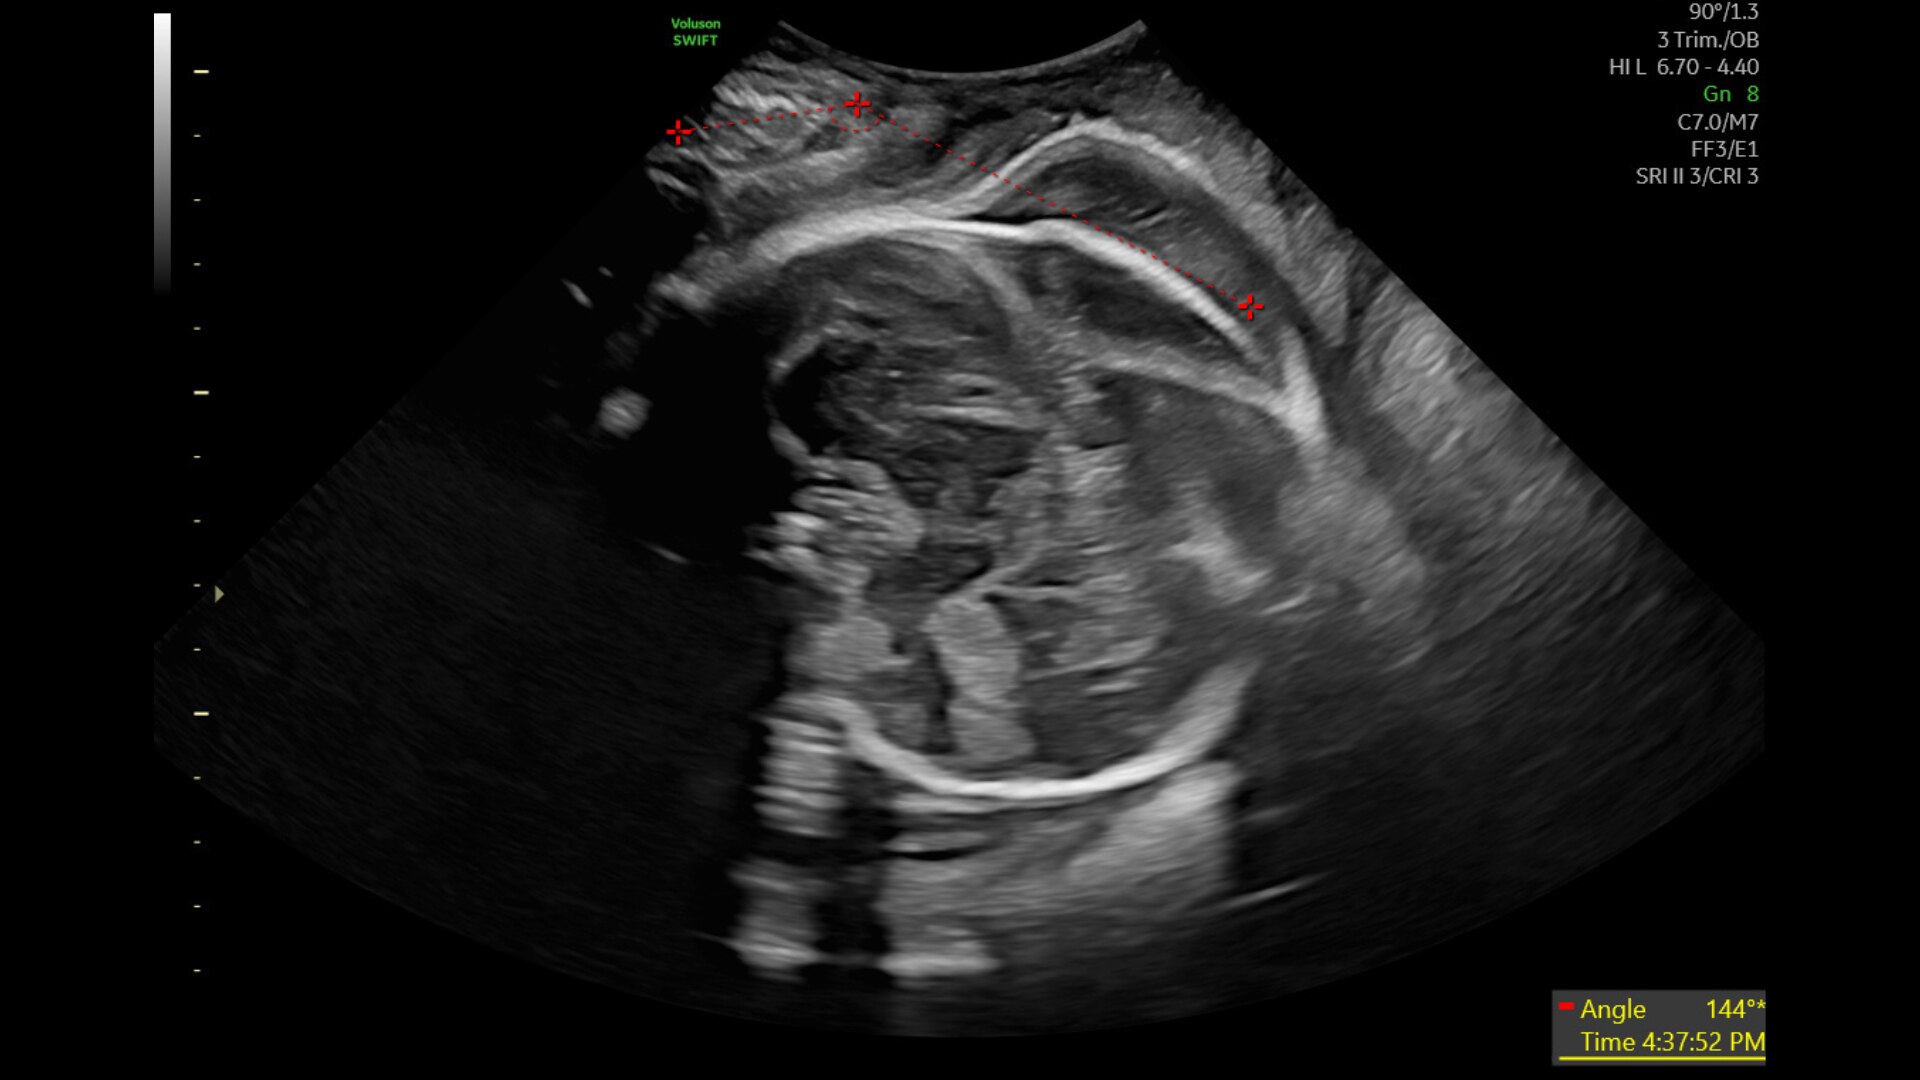

Measures & documents fetal head progression during labor

Measures and documents fetal head progression during labor

Providing objective data for reporting